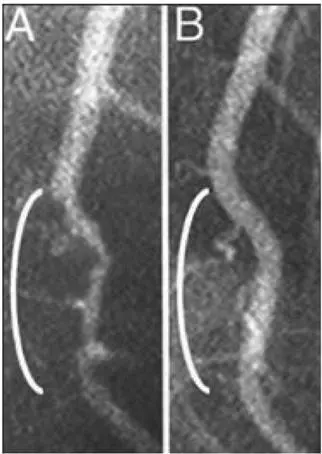

Рис. 0.2. Оба рентгеновских снимка показывают участок левой коронарной артерии, которая снабжает кровью большую часть сердца. Слева (A) можно увидеть больной сосуд (белая «трубка», которая выглядит как ветка и проходит сверху вниз, – обратите внимание на сужение в области белой скобки, как будто трубка сдавлена, что замедляет кровоток). На правой картинке (B) показан тот же самый сосуд после 32 месяцев строгой вегетарианской диеты, при которой пациент питался исключительно растительной пищей. Сужение исчезло, кровоток восстановился, артерия вновь выглядит совершенно здоровой. Болезни сосудов можно не только приостановить, но даже обратить вспять, и все это без хирургического вмешательства и медикаментозного лечения [11] См. подробнее Esselstyn (2001), Esselstyn et al. (2014), Esselstyn (2015).

.

Подобные факты подтверждают невероятную силу питания, которую мы можем контролировать самостоятельно – она буквально в наших руках. Результаты показывают, насколько основательно и глубоко можно улучшить жизнь, просто изменив рацион питания.